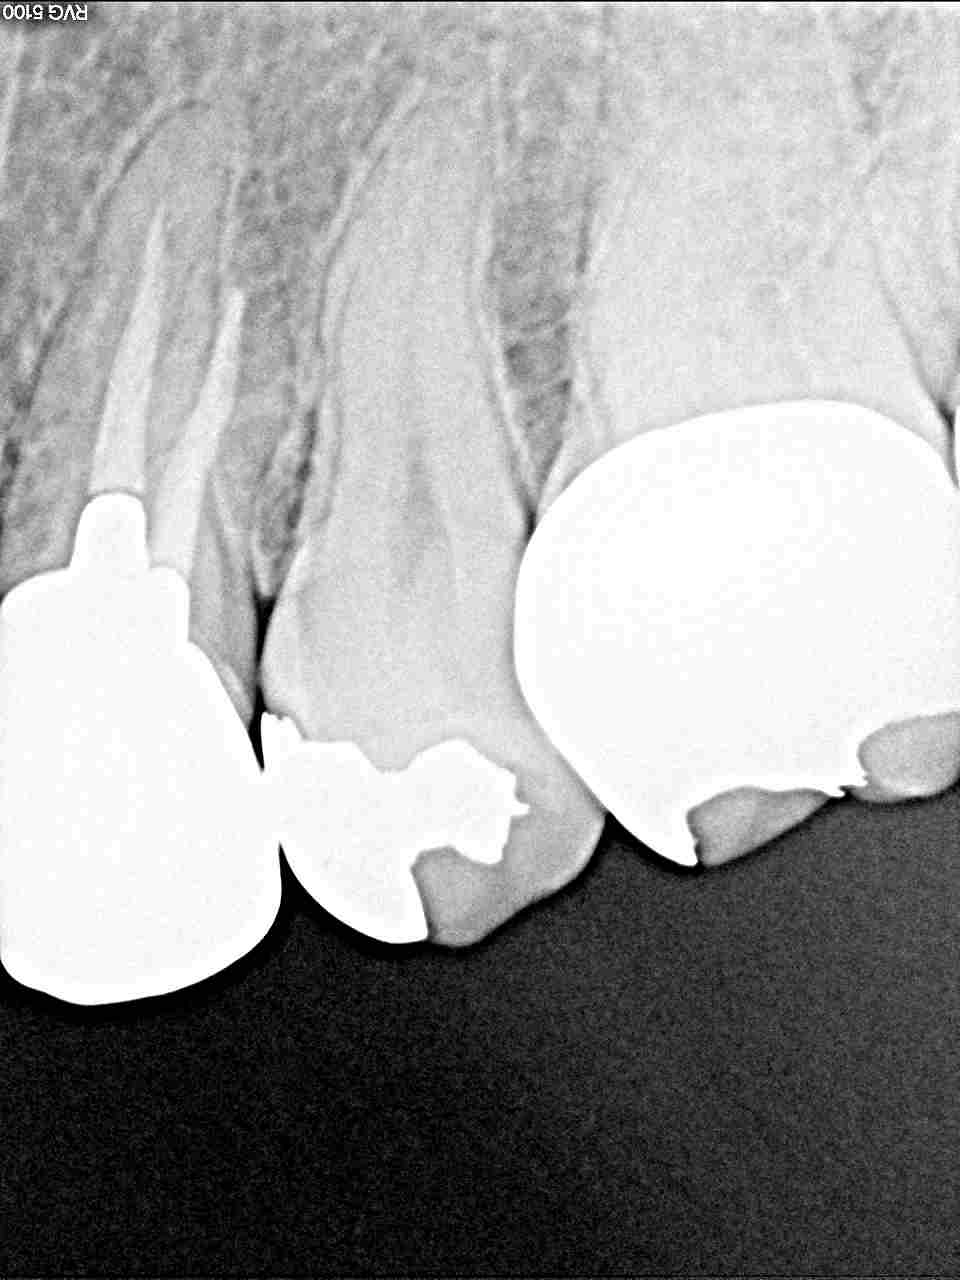

左上5番の銀歯を外して虫歯治療をしていきます |お知らせ |広島市安佐南区の歯科医院 左上5番の銀歯を外して虫歯治療をしていきます トップ お知らせ・ブログ お知らせ 左上5番の銀歯を外して虫歯治療をしていきます 左上5番の銀歯を外して虫歯治療をしていきます 銀歯の下が黒いです 虫歯の存在が疑われます レントゲンでも銀歯の境が隙間が空いています 銀歯を外していきました 虫歯が存在しています CRにて覆罩後、型取りを行いセラミックを入れていきました きれいに仕上がりました Web診療予約 初めての方へ 選ばれ続ける理由 院内設備について 歯が痛いしみる一般歯科 歯がぐらぐらする歯周病 健康な歯を保ちたい予防歯科 子供の虫歯予防をしたい小児歯科 銀歯をセラミックに審美歯科 白い歯を目指しませんか?ホワイトニング 矯正専門医がいるので安心矯正歯科 抜けた歯を補いたいインプラント・入れ歯 医院案内 スタッフ紹介 メリィハウス歯科クリニックオフィシャルホームページ ラベンダー歯科クリニックオフィシャルホームページ お知らせ・ブログ ホーム 診療科目 一般歯科 歯周病治療 予防治療 小児歯科 審美治療 ホワイトニング 矯正歯科 入れ歯・インプラント マウスピース矯正 初めての方へ 院長・スタッフ 設備紹介 医院案内・アクセス メニューを閉じる